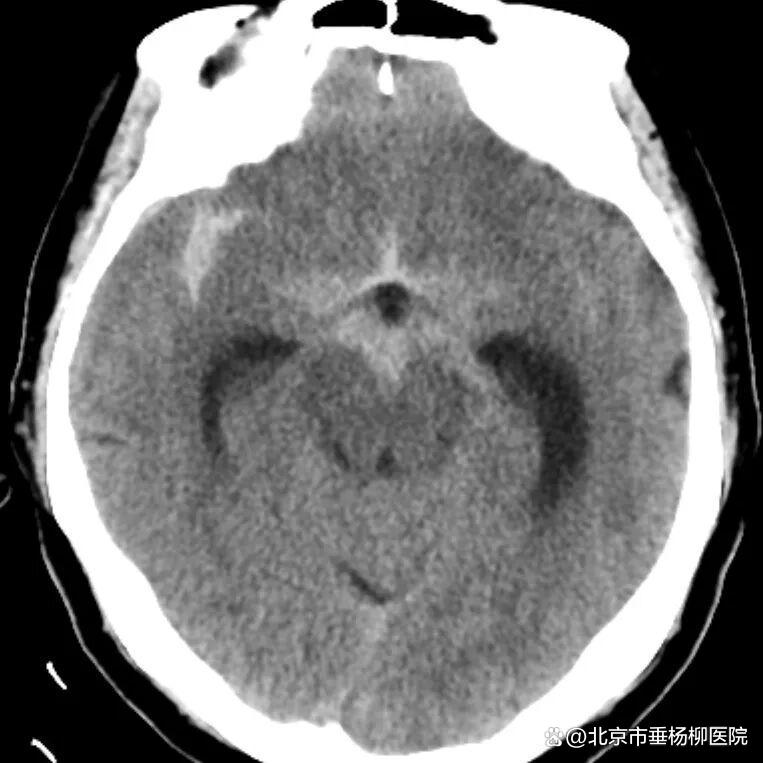

病例一为77岁女性患者,既往高血压病史。因“突发剧烈头痛伴恶心2天”前来清华大学附属垂杨柳医院急诊科就诊。头颅CT检查提示蛛网膜下腔出血,头颈动脉CTA提示右侧大脑中动脉M1段分叉处宽颈动脉瘤。神经外科脑血管病介入团队急诊为患者实施了全脑血管造影术(DSA),造影显示动脉瘤不规则,可见子囊,宽颈,主要累及下干。团队采取了支架辅助弹簧圈栓塞术,患者颅内“不定时炸弹”被成功拆除。动脉瘤达到致密栓塞,载瘤动脉通畅。住院半个月后顺利出院,无神经功能障碍。

▲头颅CT显示蛛网膜下腔出血